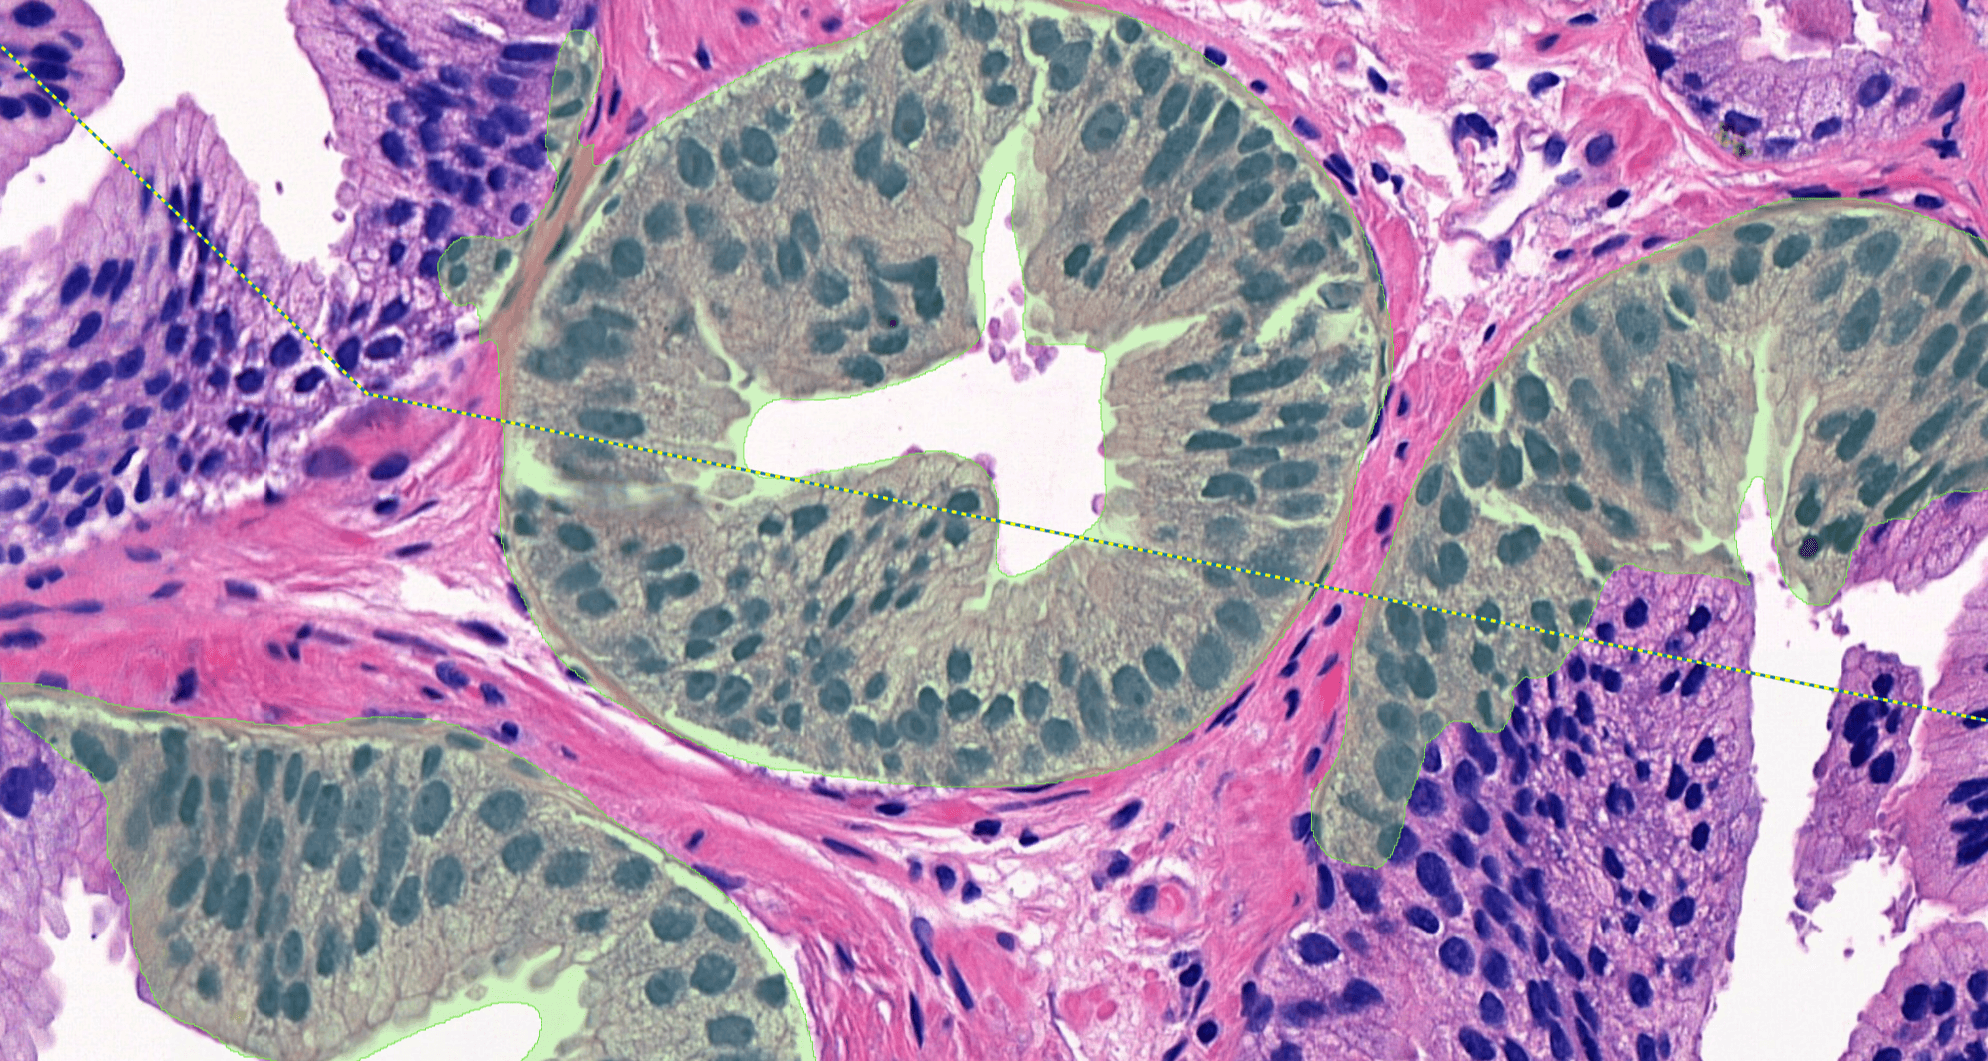

Aiforia® Prostate Cancer Suite consists of AI models with an optimized interactive user interface that supports pathologists in Gleason grade grouping and identifying adverse histopathological features.